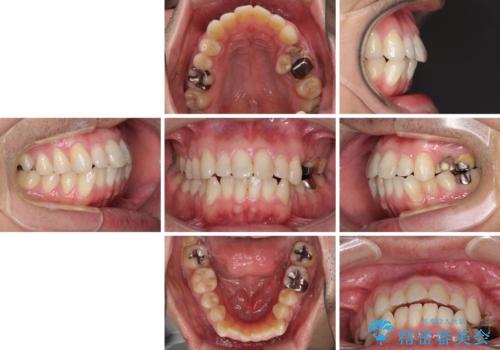

内側に転位した歯とボロボロのむし歯 インビザラインによる矯正治療とむし歯治療

- ボロボロのむし歯とデコボコの歯列を気にして来院された患者様です。

ボロボロとなっていた歯は抜歯が必要な状態でしたが、舌側転位している歯を移動させることで抜歯スペースを埋めることができるため、矯正治療により歯列を整えることとしました。

舌側転位の改善にインビザラインを用いるのはやや難易度が高くなりますが、前歯部のデコボコは軽度であったため、インビザラインによる矯正治療を行うこととしました。

矯正治療後には抜歯が必要な歯に隣接してむし歯となっていた歯をオールセラミッククラウンにて補綴治療を行うこととしました。

矯正治療開始時に、インビザライン矯正の加速装置を購入されましたが、インビザライン自体をあまりしっかりと使用できず、4年間の治療期間となりました。